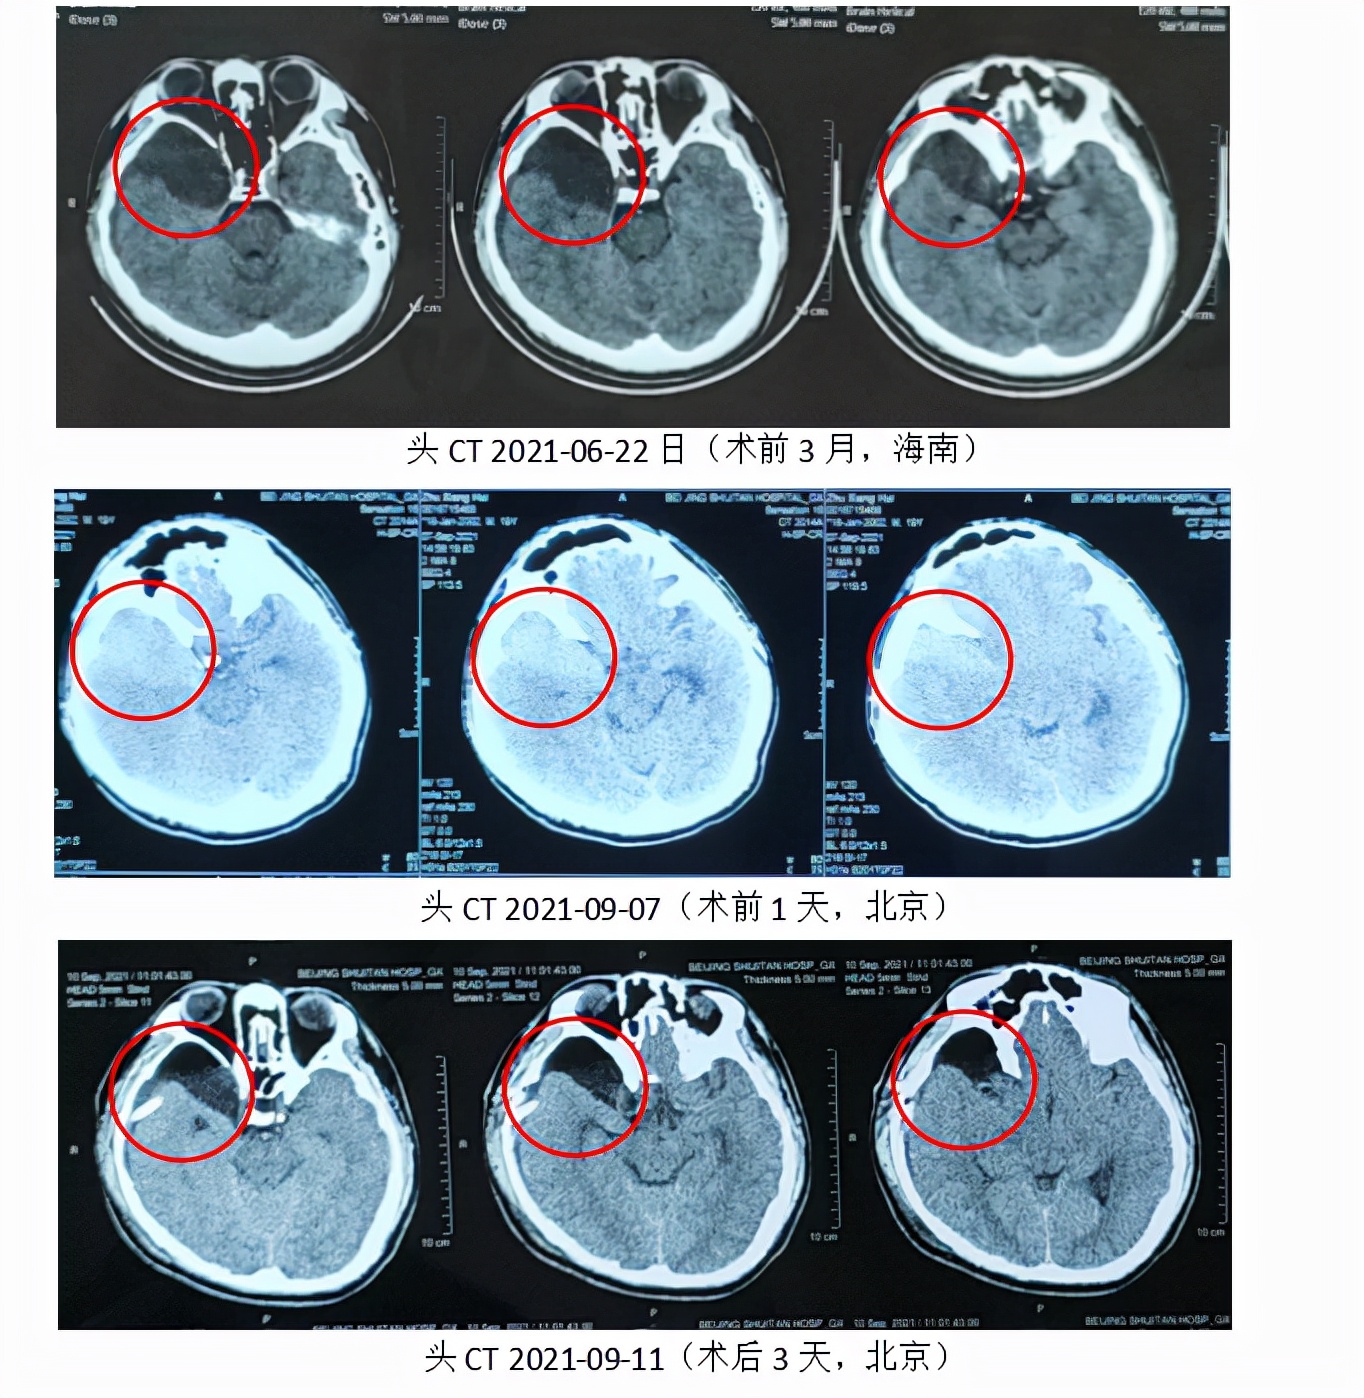

暑假回海南老家,头疼还是经常发作,在海南做头部CT检查后,诊断是“先天性囊肿”和“积液”,定期复查即可。但回到北京上学后,头疼愈演愈烈,有时还伴有恶心呕吐,于是来到北京世纪坛医院神经外科就诊。胡志强主任安排了头部CT检查,结果居然发现了“硬膜下血肿”,且血肿量还不少,需要手术治疗。若脑子出了问题,就算勉强能念书,体能训练恐怕也完成不了,患者的警官梦是否要从此化为泡影?

自发病以来,该患者精神状态差,饮食差,入院时患者头疼明显加重,伴恶心呕吐,头CT提示“硬膜下及蛛网膜囊肿内较多高密度影,中线移位,考虑亚急性硬膜下血肿”,具备手术指征。

经过精心的手术方案讨论设计,手术顺利完成,内镜微创手术解决了“蛛网膜囊肿+硬膜下血肿”双重病痛,且没有留下任何神经系统症状。术后1周患者头部CT提示,引流管位于囊肿内,囊肿体积较术前缩小,其内血肿已完全清除,硬膜下血肿明显减少。仅仅术后2周,患者已经开始了文化课的学习,术后1月患者已经开始接受了基础的训练课程。